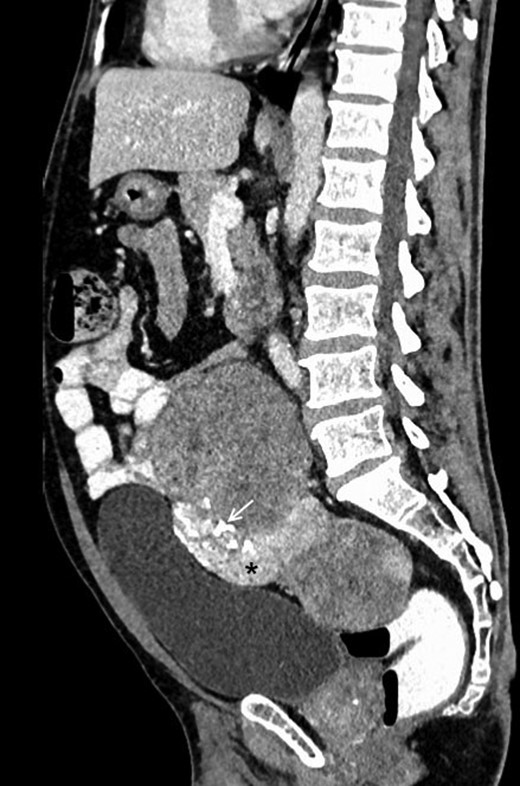

A 48-year-male patient presented with awareness of gradually increasing lower abdominal lump and abdominal discomfort for 8 months. There was no history of anorexia and weight loss. He was a non-smoker and non-alcoholic. His general physical examination was unremarkable with no clinical evidence of hepatic disease and adrenal or pituitary insufficiency. On abdominal examination, about 8 × 10 cm non-tender, hard, well-defined intra-abdominal lump was present in hypogastrium, which was extending into right iliac fossa, right lumbar and umbilical region for which the lower margin was not palpable. The lump was bimanually palpable on rectal examination. It was causing intra-luminal projection within rectum without any mucosal irregularity. His initial basic laboratory investigations which included hemogram, coagulogram, blood sugar, serum sodium, potassium, chloride, calcium, renal and liver function tests and urine analysis were within normal range. CECT abdomen (Figs 1 and 2) revealed a 20 × 15 × 7 cm heterogenous well-defined lobulated mass with calcification and areas of necrosis in the pre-sacral region and was extending superiorly up to the lower border of L3. It was indenting into the bladder anteriorly and rectum posteriorly, also abutting pelvic vessels but maintaining fat planes with all these structures. This mass was causing bilateral hydroureteronephrosis.

Contrast-enhanced sagittal reformatted CT section of the abdomen depicts a large enhancing mass posterior to the urinary bladder and anterior to the lower lumbar vertebrae and sacrum. The lesion is heterogeneously enhancing with a small hyperenhancing component (asterisk). Foci of calcification are noted within the lesion (white arrow). Note that the fat planes with the bowel and the urinary bladder are maintained.